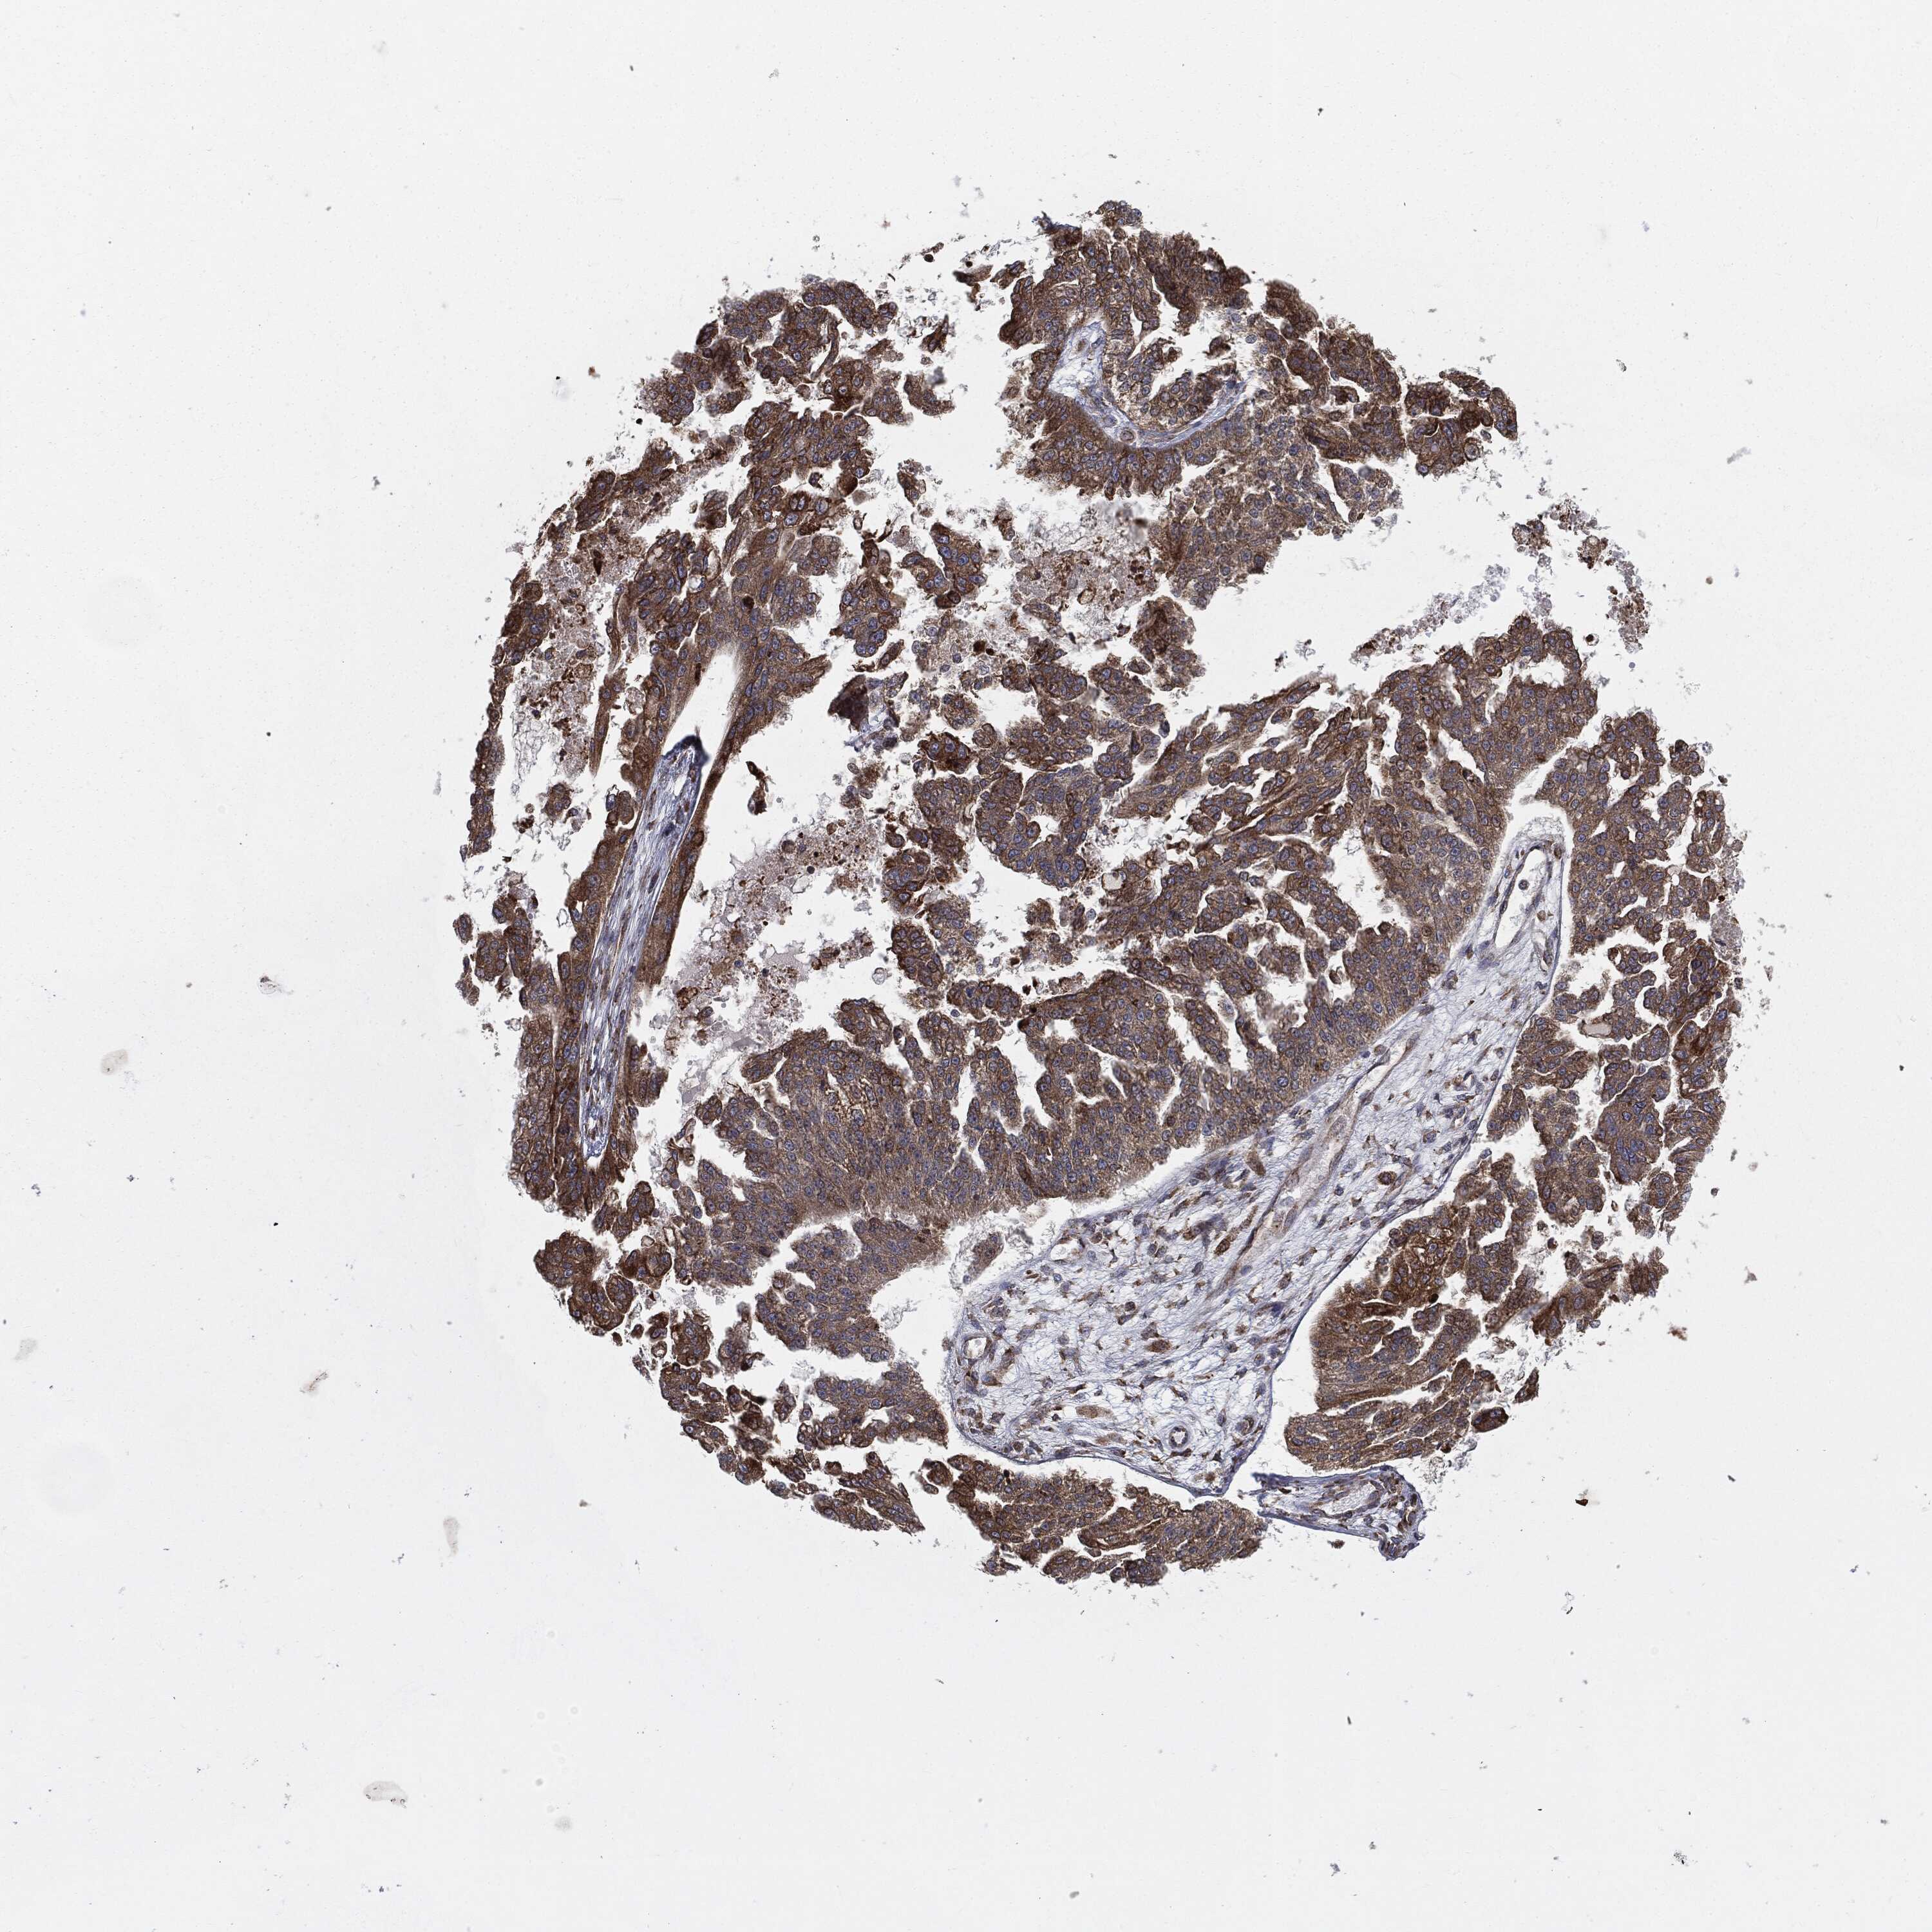

OVARIAN CANCER - Protein expressioni

A mouse-over function shows sample information and annotation data. Click on an image to view it in a full screen mode. Samples can be filtered based on level of antibody staining by selecting one or several of the following categories: high, medium, low and not detected. The assay and annotation is described here.

Note that samples used for immunohistochemistry by the Human Protein Atlas do not correspond to samples in the TCGA dataset.

Antibody stainingi

Antibody staining in the annotated cell types in the current human tissue is reported as not detected, low, medium, or high, based on conventional immunohistochemistry profiling in selected tissues. This score is based on the combination of the staining intensity and fraction of stained cells.

Each image is clickable and will lead to virtual microscopy that enables deeper exploration of all samples and also displays staining intensity scores, fraction scores and subcellular localization as well as patient and tissue information for each sample.

Antibody HPA077163

Antibody CAB011713

Staining

High

Cystadenocarcinoma, serous, NOS